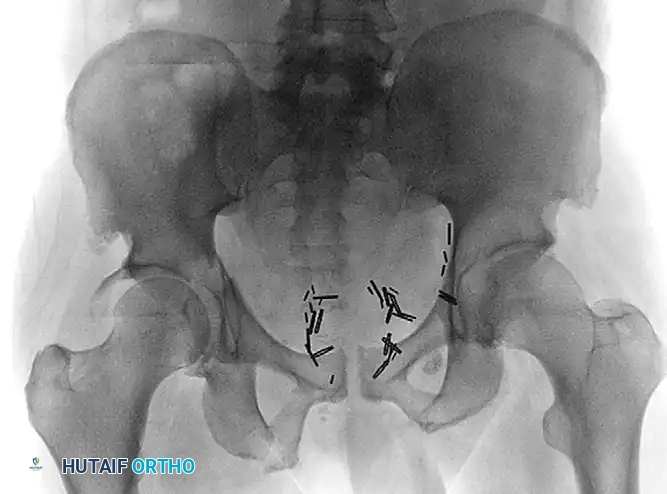

Preoperative anteroposterior (AP) radiograph demonstrating a complex transverse posterior wall fracture in an elderly patient, characterized by significant displacement and articular incongruity.